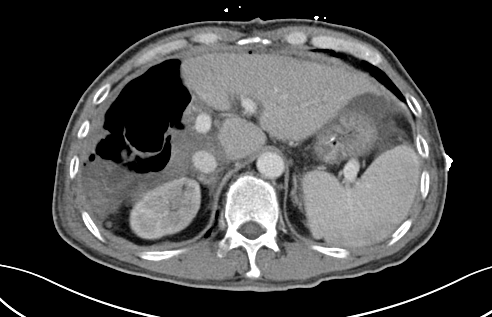

術前CT

近段時間,他因右上腹疼痛就診于瀘州市中醫(yī)醫(yī)院,在檢查中發(fā)現(xiàn)右側(cè)肝臟有一12公分左右的包塊,初步考慮為惡性腫瘤,后收治入院。通過全面檢查,診斷其為肝癌晚期,并伴有乙型肝炎、肝硬化等病癥。

“該患者入院后,通過肝臟CT,我們發(fā)現(xiàn),由于其右肝腫瘤巨大,而正常的左肝體積比較小,手術預切除肝體積達70%以上,術后殘肝體積僅28.3%,再加上該患者存在乙肝和肝硬化,剩余肝臟不足以維持他身體正常運轉(zhuǎn)所需,不具備肝臟手術切除的基本要求?!焙鷤ケ硎尽?/span>